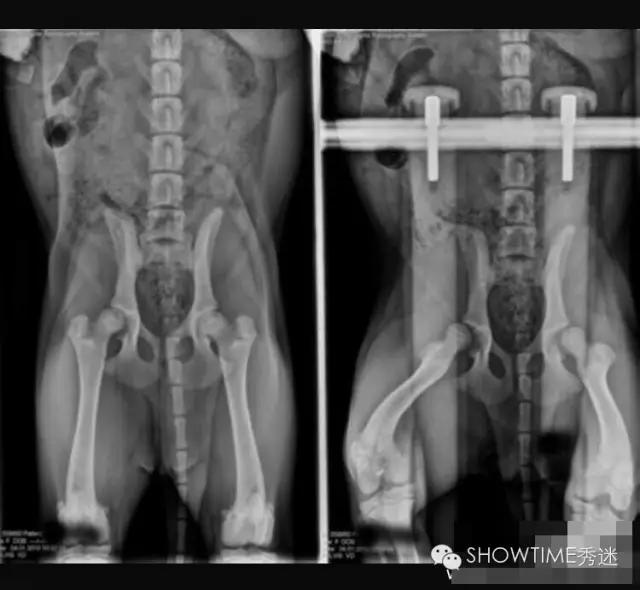

针对髋关节发育不良的判定,犬类骨科疾病种类很多,并非所有走路摇摆外八或者无力都是CHD。OFA组织是根据X光片来进行判断的,在犬只年满24月龄以后才会给出评判结果,24个月之前只做评估不做判定。因为犬在两岁前还在发育,股骨头和髋臼常会出现发育速度不一而产生髋关节发育不全的现象,这其中还要受到肌肉的影响。并且也有幼犬时期髋关节发育正常,而后随着成长过程发生严重变化,进而产生CHD症状,因此判定:只有在24月龄之后才可以做出。这是在美国和全世界至今应用最为广泛的方法,也是美国繁殖者在繁殖中的主要依托。

在髋关节发育不良的诊断中有一个最为重要的因素,就是X光片的拍摄要求。在国内很多医院因此而产生的误诊不胜枚举。